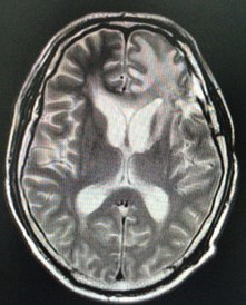

查头颅增强MR(2017-10-27,本院):示左侧额叶异常信号,考虑转移

T2:

头颅MRI(2018-02-08,本院)左侧额叶、叶脑软化灶;左侧基底节区慢性脑梗死;双侧额叶、右侧颈叶、左侧基底节区缺血性改变;老年性脑改变;右侧乳突炎